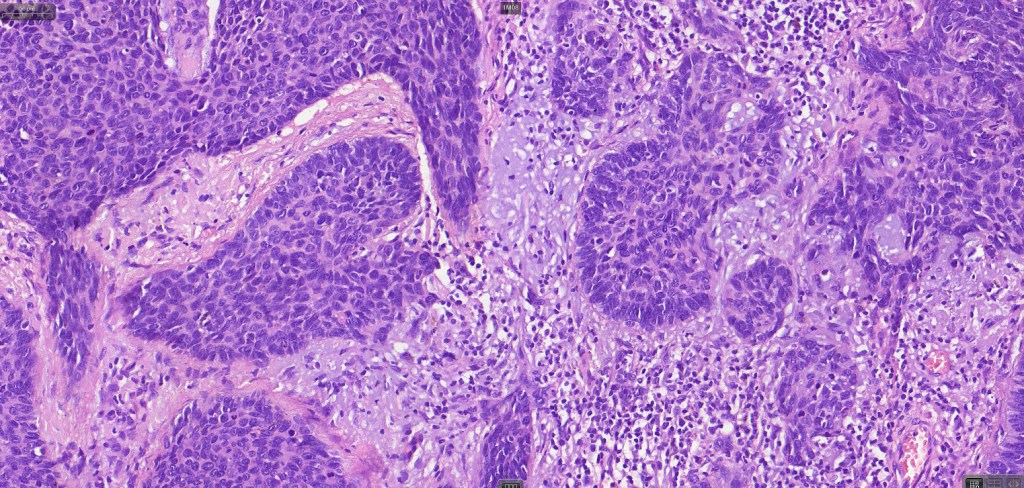

•The epithelial component is composed of uniform small, basophilic devoid of desmosomes

•Peripheral palisading

•Retraction artifact with stromal mucin

•Pseudoglandular appearance

•Mitoses often very marked

•Apoptosis

•A wide variety of histological variants are possible including nodular, nodulocystic, ulcerative, superficial, micronodular, infiltrating/infiltrative, keratotic, basosquamous, pigmented, morpheaform, keloidal, clear-cell, signet-ring cell & granular cell variants, BCC with monster cells, BCC with metaplastic features, BCC with matricial differentiation, basomelanocytic tumor (see separate blog), BCC with thickened basement membrane, BCC with carcinoid-like nuclear palisading & these are illustrated below